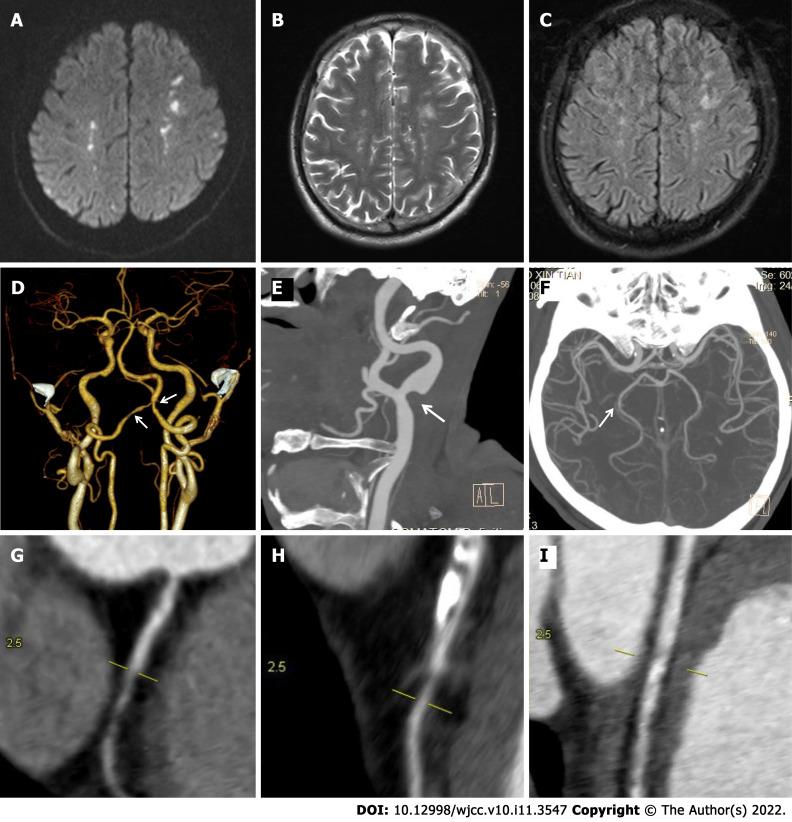

A 64-year-old male patient was admitted with headache and right lower extremity weakness. Laboratory tests indicated eosinophilia. Brain magnetic resonance imaging (MRI) showed bilateral and multiple acute infarcts in the border zones. Electrocardiography revealed that T wave was inverted and that the concentration of troponin I was significantly elevated above normal levels. Cardiac echocardiography showed an ejection fraction of 69% with mitral and tricuspid mild regurgitation. Computed tomography angiography detected multiple and localized instances of mild stenosis in the left common carotid artery bifurcation, bilateral vertebral arteries (V5 segment), and the posterior cerebral artery (P2 segment). These were observed together with multiple non-calcified and mixed plaques as well as luminal stenosis in the left circumflex artery, left anterior descending artery, and right coronary artery. The patient was treated with oral methylprednisolone and clopidogrel, after which the absolute eosinophil count fell rapidly to a normal level. After one month, a second brain MRI showed a partial reduction in the size and number of the lesions.

HES can masquerade as ischemic stroke, myocardial infarction, and arterial vascular involvement. The patient reported here recovered very quickly when his eosinophil blood count returned to normal. Early diagnosis and rapid reduction of eosinophils may lead to a good prognosis.